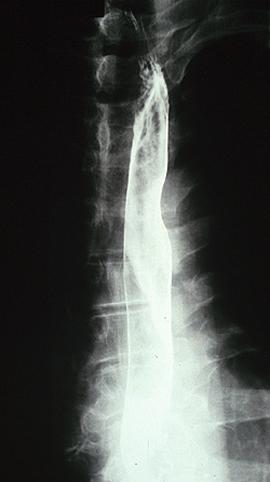

部位(按器官分)食道/2个以上

检查方法X线

肿瘤的肉眼分类0型(表在型)/其他

肿瘤最大直径40以上

肿瘤的深度sm